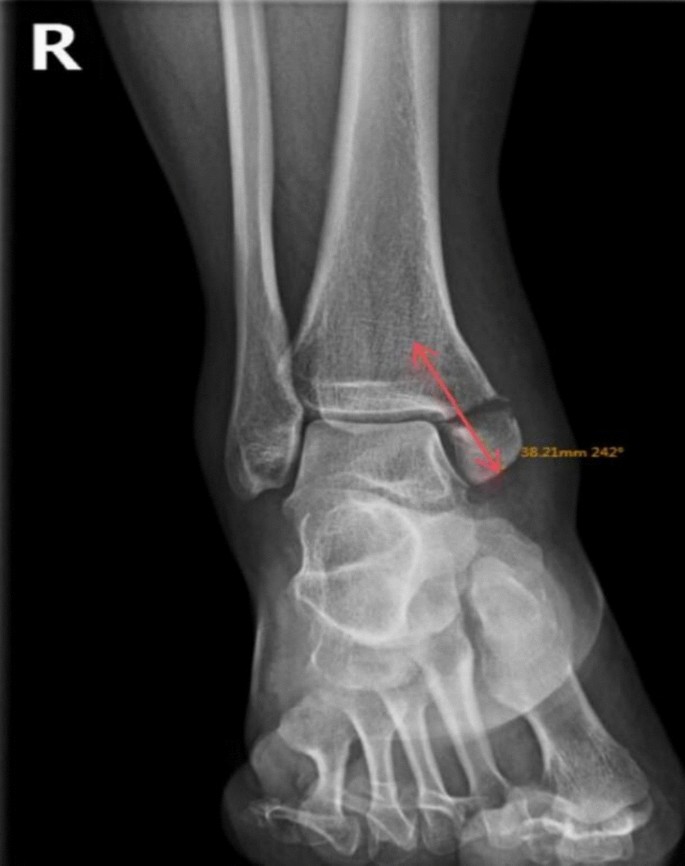

In the ARPF Group: All surgeries were performed under combined spinal-epidura anesthesia in the supine position. The surgical area was sterilised, a pneumatic tourniquet was applied. During the operation, A 2.7 mm, 30°arthroscope (Smith & Nephew, Andover, MA) was inserted into the ankle through a standard anteromedial portal, afterwards the standard anterolateral portal is performed in the same way. The cannula was used to protect tissue and guide the arthroscope into the joint cavity, if the joint space is narrow, an assistant assisted in traction of the ankle joint to increase the joint space. A systematic 21-point arthroscopic examination was performed to assess the articular anatomical structure, intraoperative treatment was performed according to the degree of ligament fiber tear and the depth of cartilage injury(two patients were found to have talar cartilage injury during the operation, The depth of the articular cartilage lesions was graded according to ICRS (International Cartilage Repair Society) arthroscopic grading system, two patients exhibited Grade II talar cartilage injuries, which were managed with microfracture. Partial tear (grade II per Park criteria) of the medial deltoid ligament was found in three patients and were treated with electrocoagulation and tightening. None of the patients had syndesmotic ligament injuries). Before reduction, hemarthrosis and debris were meticulously debrided by a high-speed shaver to expose fracture line (Fig. 1). At the distal end of the medial malleolus, a towel clamp was used to hold the fracture fragment, and with the help of the towel clamp, the fracture fragment was pushed proximally to go near the proximal tibia. Under the monitoring of the arthroscope, a hook needle was used by leveraging or pushing to achieve anatomic reduction. After observing under the arthroscope that the joint surface at the fracture site was smooth, towel clamps were used to temporarily fix both ends of the fracture, at the same time, a K-wire was drilled into the fracture site for temporary fixation. Then, two guide wires were drilled on both sides of the K-wire through the fracture sites, two 3.5 mm cannulated screws were driven over the guidewires (Fig. 2), the length and direction of each screw was measured by using preoperative radiographs and computed tomography scans (Fig. 3). Under the arthroscope, the smoothness of the medial joint was observed and evaluated, and it was checked whether the internal fixators penetrated the joint surface (Fig. 4). Finally, if the length and position of the screw was not certain intraoperatively, fluoroscopy was performed to confirm them.

Operative indicators: including intraoperative blood loss, operation time, fracture healing time. X-ray examination was performed regularly after surgery. If the examination shows that the fracture line has disappeared and the callus has formed extensively, the fracture was considered to be healed.